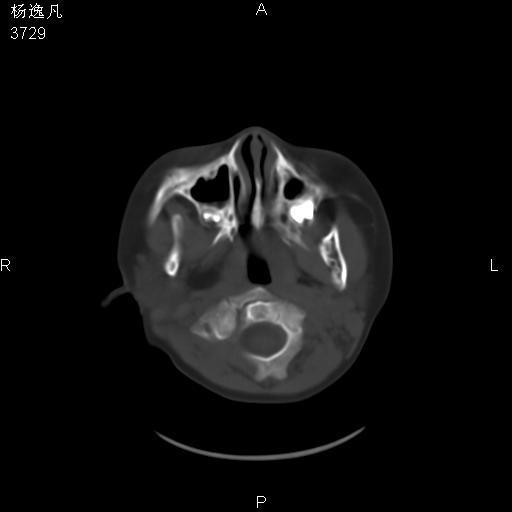

男性,5岁,面部受外伤,余无特殊

软组织窗

1、右面部及颞部软组织肿胀。

2、腺样体肥大。

头颅ct平扫未见明确外伤性征象,右侧面部及颞部软组织肿胀,后鼻腔软组织影增大,增厚,鼻咽顶部变窄,考虑鼻咽腺样体增值肥厚。